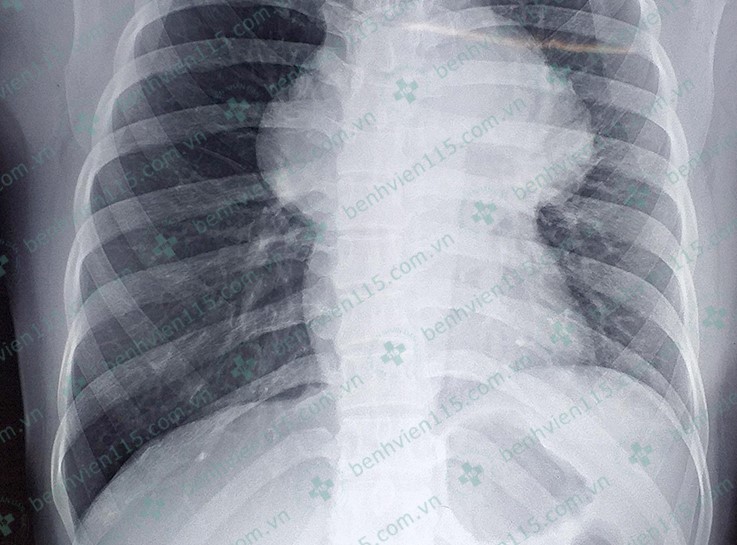

Anh chụp X-quang cho thấy khối u trung thất chiếm trọn lồng ngực bệnh nhân. Ảnh:BSCC

Kết quả chụp chiếu cho thấy có 1 khối choán chỗ vùng trung thất, chèn ép tĩnh mạch chủ trên, tĩnh mạch thân cánh tay đầu phải và các mạch máu vùng rốn phổi hai bên, có ít dịch màng ngoài tim.

- Khối u có trọng lượng 2 kg chiếm gần hết lồng ngực khiến cô gái thường thấy mệt, khó thở và phải ngủ ngồi.